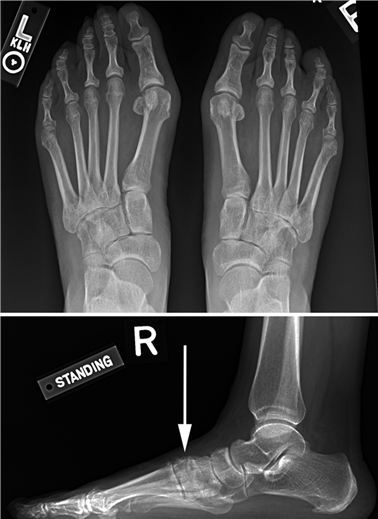

Weight-bearing anteroposterior (AP), lateral, and sesamoid axial radiographs are mandatory. On the AP view, the surgeon measures the Hallux Valgus Angle (HVA, normal < 15°), the Intermetatarsal Angle (IMA, normal < 9°), and the Distal Metatarsal Articular Angle (DMAA). The lateral view is scrutinized for Meary's angle (talo-first metatarsal angle) to identify midfoot collapse, as well as the presence of dorsal osteophytes indicative of hallux rigidus. The sesamoid axial view is critical for assessing the degree of sesamoid subluxation and the integrity of the crista.

Image